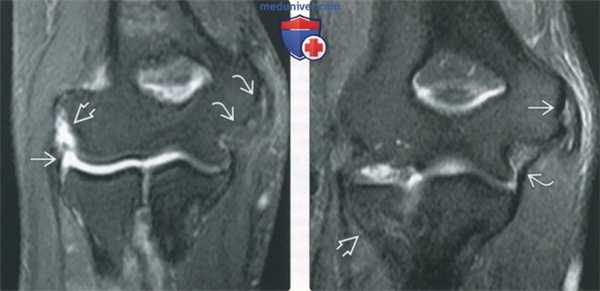

(Слева) МР-артрография в режиме Т2ВИ FSE FS, сагиттальный срез: визуализируются «целующиеся» ушибы передней поверхности головки лучевой кости и задней поверхности головки мыщелка плечевой кости, обусловленные перенесенным ранее задним вывихом головки лучевой кости. В этом случае отличить травматический дефект головки мыщелка плечевой кости от псевдодефекта позволяет наличие отека костного мозга.

(Справа) МР-артрография в режиме Т2ВИ FSE FS, коронарный срез, этот же пациент: отмечаются дефект хряща, импрессия субхондрального отдела кости и перифокальный отек костного мозга.